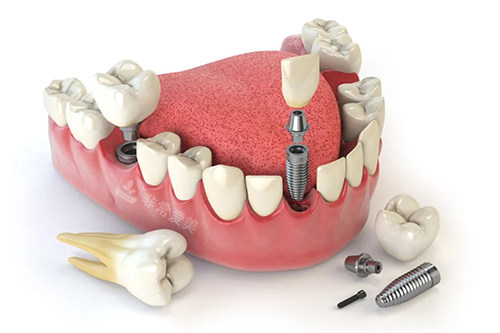

种牙和矫正是吉林市德立联合口腔的两大特色项目。

在种牙方面,医院拥有经验充足的种植医生团队,他们熟练掌握各种种植技术,能够根据患者的不同情况选择合适的种植方案。

无论是单颗牙缺失还是多颗牙缺失,都能为患者提供优质的种植服务。

而且,医院使用的种植体质量可靠,术后结果良好,能让患者修复正常的咀嚼功能。